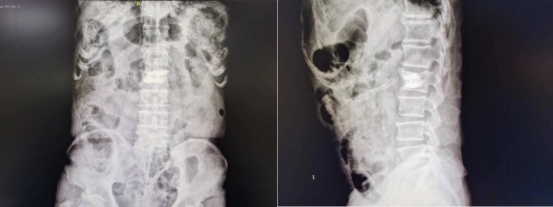

通过系统科学的围手术期管理,老人各项指标均达到手术要求。在麻醉科医师的严密生命体征监护下,王岩松带领程道林仅用时30分钟,利用X线反复透视定位,通过直径仅2.5mm的穿刺针,精准地向病椎中注入骨水泥,并严格控制注入量避免了骨水泥渗漏,手术结束后患者腰部仅有2个芝麻大小的针孔,无需缝合。术中患者未出现任何不适,术中及术后X线影像学检查证明骨水泥灌注满意,椎体已恢复高度。

术后复查X线可见骨水泥填充满意无渗漏,椎体高度已恢复